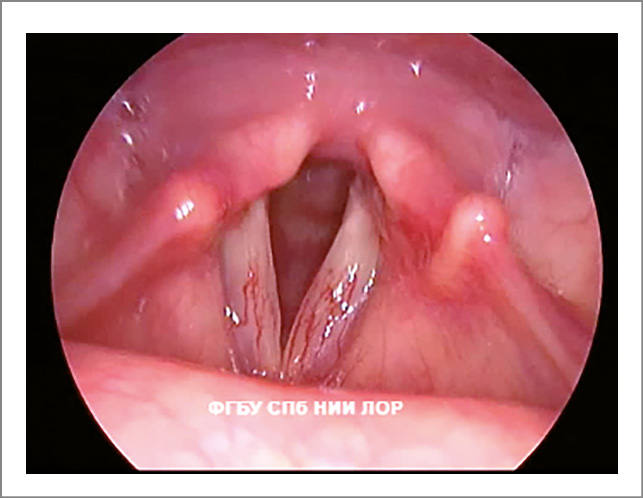

- Фонационная щель пациентов с функциональной дисфонией не соответствует форме фонационной щели здоровых людей. Изменение формы фонационной щели – основной признак гипотонуса голосовых складок. Сниженный тонус мышц гортани проявляется овальной, широкой линейной или треугольной фонационной щелью. Если у пациентов с функциональной дисфонией форма фонационной щели напоминает овал, то это свидетельствует о преимущественном снижении тонуса голосовых мышц (рис. 1). При снижении тонуса межчерпаловидных мышц фонационная щель имеет вид треугольника с верхушкой в передней комиссуре и основанием в межчерпаловидной области (рис. 2).

Рис. 1. Функциональная дисфония по гипотонусному типу (фонация): овальная щель.